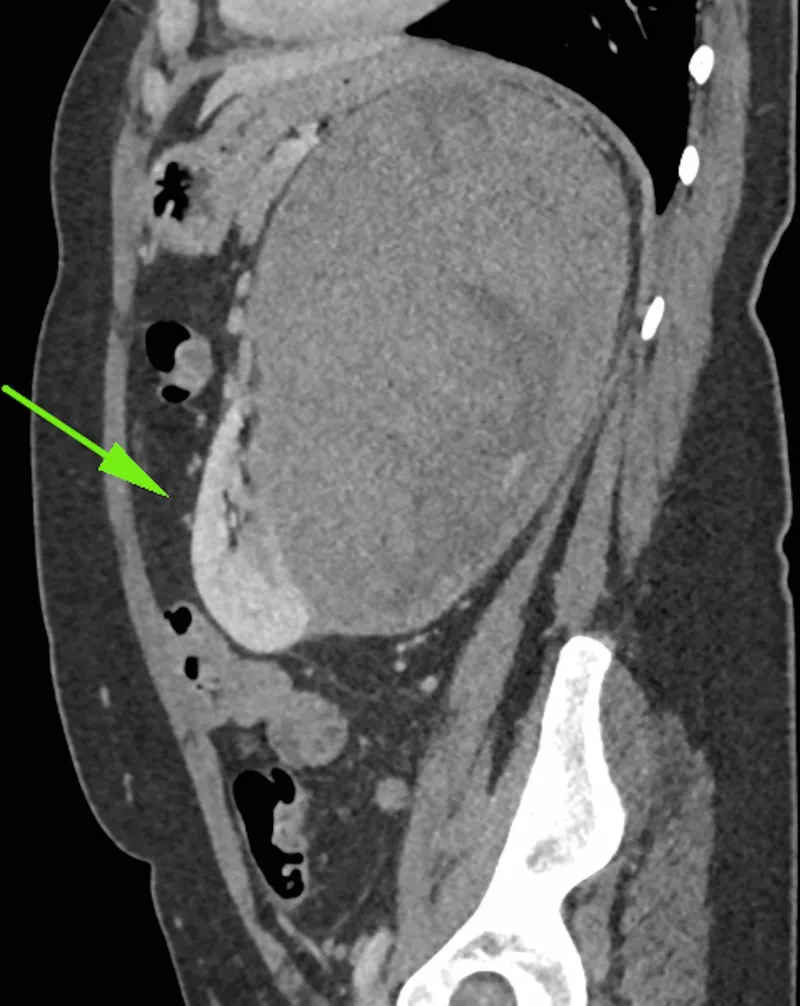

Wilms Tumor - Kidney Kidnappers

- Origin: Metanephric blastema (embryonic kidney cells).

- Age: Peak 3-4 yrs; 90% diagnosed < 7 yrs. Usually unilateral.

- Presentation: Asymptomatic abdominal mass (most common; smooth, firm, rarely crosses midline). Hematuria, hypertension (renin ↑), abdominal pain, fever.

⭐ Bilateral Wilms tumor occurs in 5-10% of cases, often has an earlier age of onset, and frequently requires modified treatment protocols including neoadjuvant chemo.